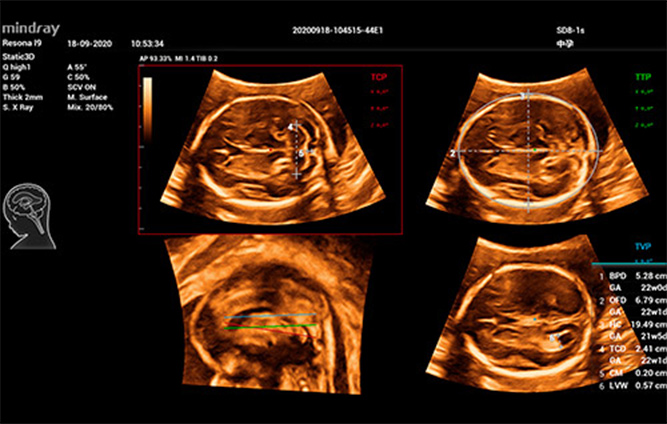

Tijdens de zwangerschap is echografie voor moeders een rechtstreekse manier om te weten hoe het leven van de foetus in de baarmoeder verloopt: hoe het kind groeit, of het lichaam zich ontwikkelt en of de placenta en het vruchtwater in goede staat zijn: allemaal zaken die van invloed zijn op het hart van de moeder.

De geringe doeltreffendheid van echografisch onderzoek van de foetus, als gevolg van de verschillende plaatsen en metingen, heeft echografisten echter lange tijd parten gespeeld . Bij 3D/4D-echografisch onderzoek wordt veel belang gehecht aan ultrasone foetusdiagnose, waardoor artsen de ruimtelijke locatie van structuren in meer detail kunnen vaststellen. De veranderende positie en beweging van de foetus, de gecompliceerde aanpassing van de parameters en de omslachtige operationele stappen hebben echter een aanzienlijke invloed op de kwaliteit en de effici?ntie. We denken al lang na over hoe de consistentie en herhaalbaarheid van 3D-echografisch onderzoek kan worden verbeterd om een nauwkeurige diagnose te stellen.

Om de afhankelijkheid van de gebruiker te verminderen en de effici?ntie van de diagnose te verbeteren, heeft Mindray een innovatieve, op klinische scenario's gebaseerde 3D/4D-interactie ontwikkeld voor typische klinische scenario's van 3D-echografieonderzoeken, zoals de hersenen, het gezicht, de wervelkolom en de lange botten van de foetus. Hiermee is met slechts ├®├®n klik automatische sc├©ne-identificatie, automatische beeldoptimalisatie, automatische vlakkenacquisitie en automatische kwantificatie mogelijk. Het zorgt echt voor een automatische workflow gedurende de hele procedure, wat een sterk diagnostisch vertrouwen geeft voor betere pati?ntenzorg.

Smart Planes CNS

Smart ICV: Automatische berekening van intracraniaal volume